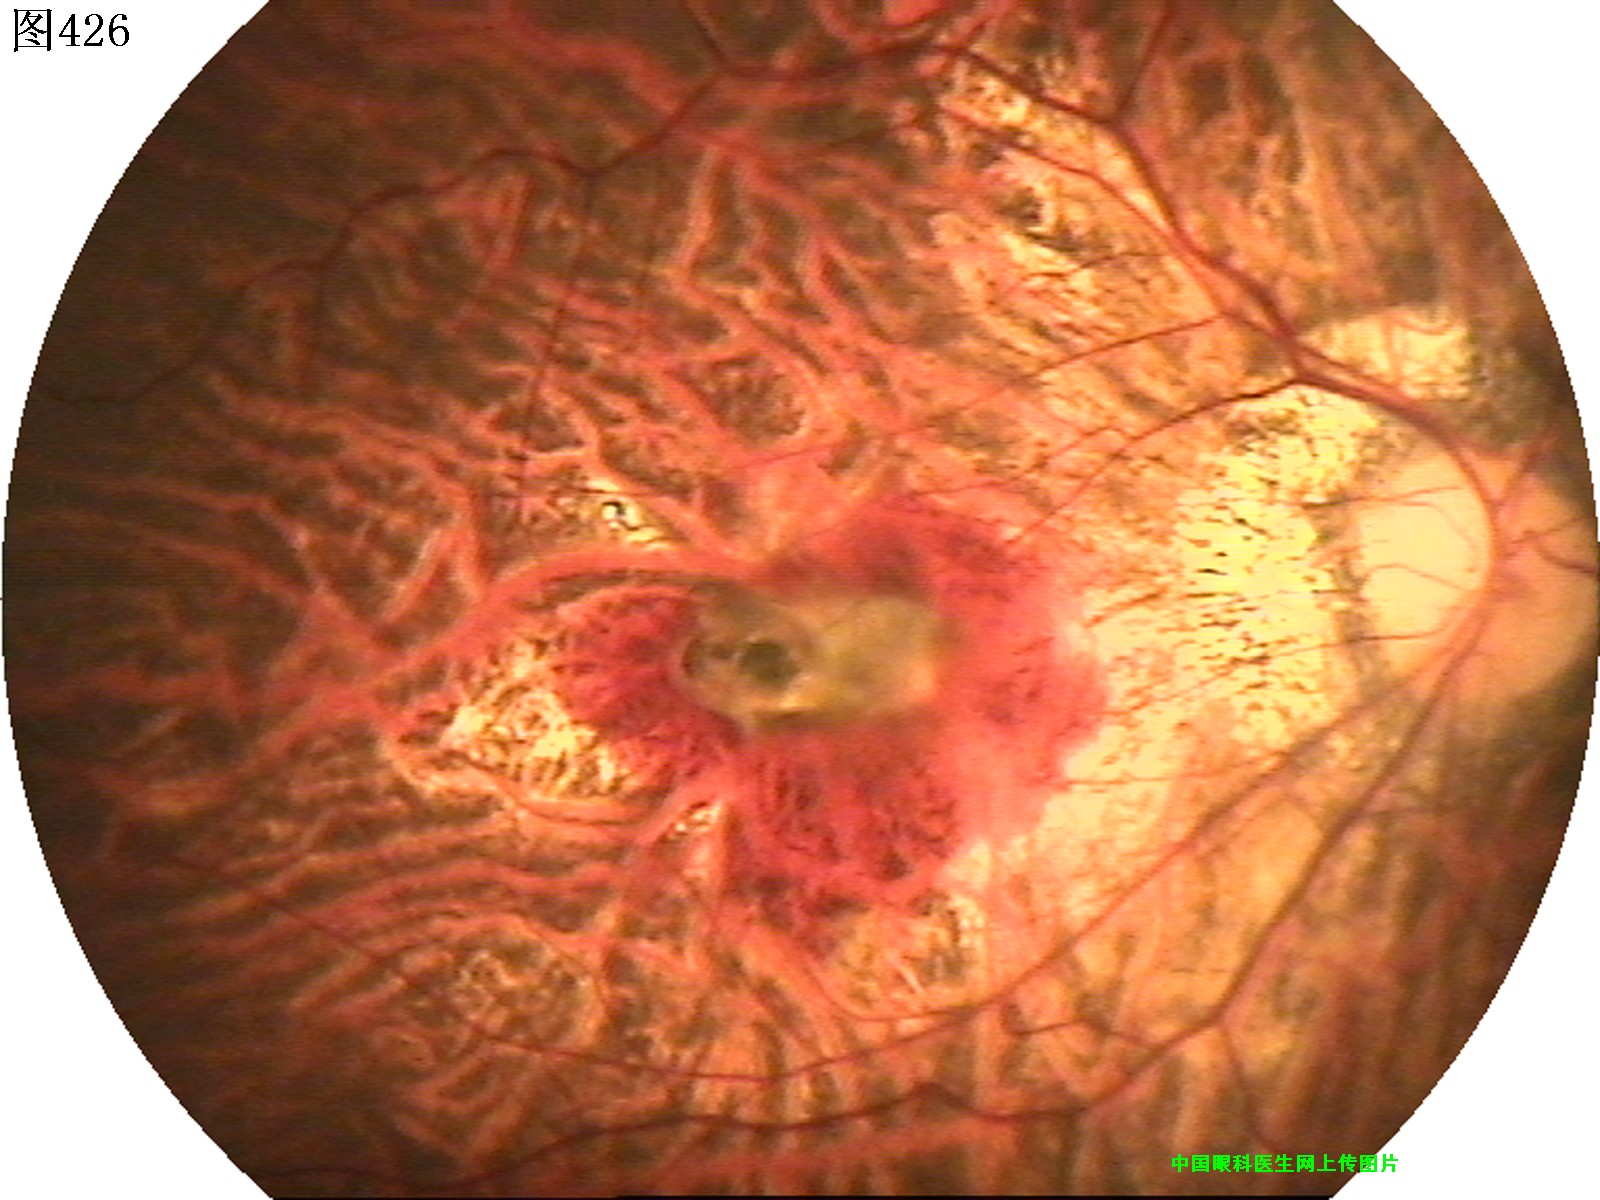

425 426 427 428